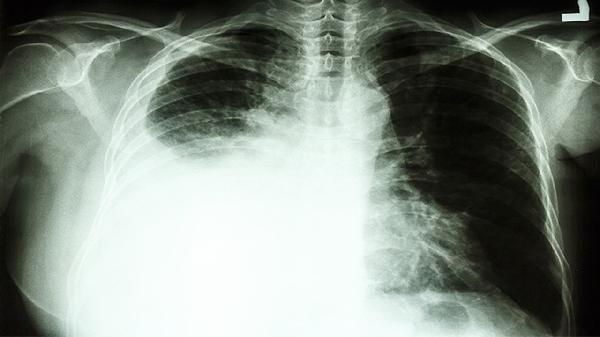

肺癌患者应优先遵循规范化诊疗方案,定期复查评估疗效。若需联合中药调理,须由中医肿瘤科医师辨证施治。日常需保证优质蛋白摄入,适当进行呼吸功能锻炼,避免吸烟及二手烟暴露。心理疏导与营养支持同样重要,可帮助提升整体治疗效果。